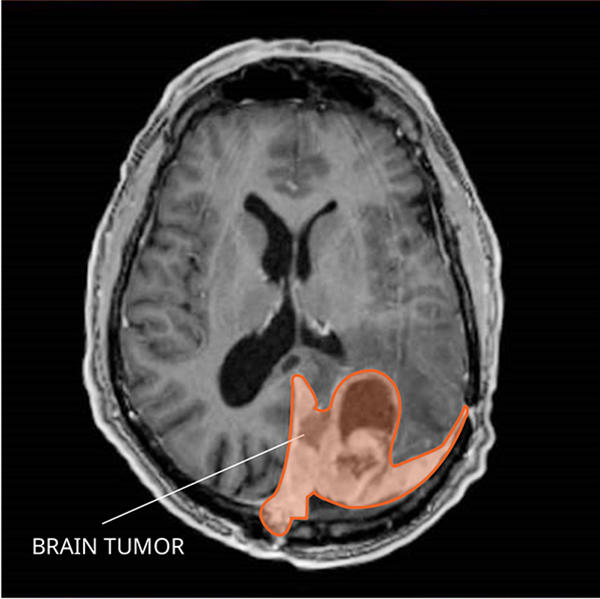

What do atypical and anaplastic meningiomas look like on an MRI?

Grade II and III meningiomas usually appear as an enhancing mass on the outside lining of the brain tissue, which may or may not brighten with contrast. Malignant meningiomas can also invade into the brain tissue.